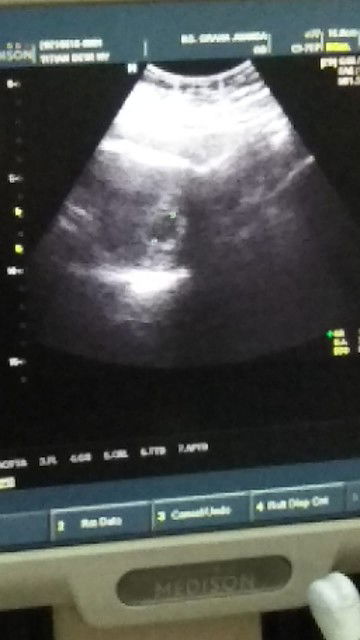

Malam bunda- bunda mau nanya dong saya tanggal 18 Mei 2021 kemarin melakukan tespek dan hasilnya positif, lalu Sore harinya saya ke dokter kandungan dan dilakukan USG Namun kata dokternya yang terlihat baru kantong kehamilan dan kehamilannya ada di dalam rahim. Saya disuruh balik lagi satu bulan kemudian atau sekitar tanggal 18 Juni 2021. (Dokternya sempat nyeletuk, kita lihat sebulan dulu takutnya ini kehamilan kosong) jujur bund saya sempat down gitu cuma tetap berfikir yg positif2 aja. Menurut bunda-bunda hal itu normal nggak? saya harus gimana ya, ada saran kah dari bunda -bunda sekalian ? Oya bund...info saja..ini kehmilan pertama setelah penantian 7 thn 😭😭😭 terimakasih #seriusnanya #bantusharing #ingintahu #jangandibully #firstbaby #pleasehelp